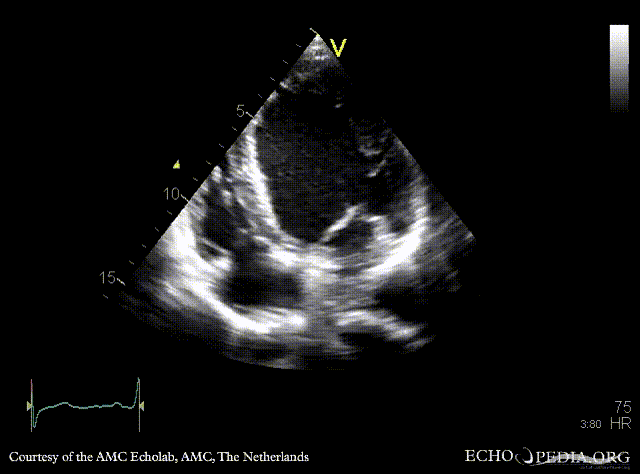

PLAX: dilated left ventricle and ascending aorta in patient with Marfan syndrome PLAX: dilated ascending aorta